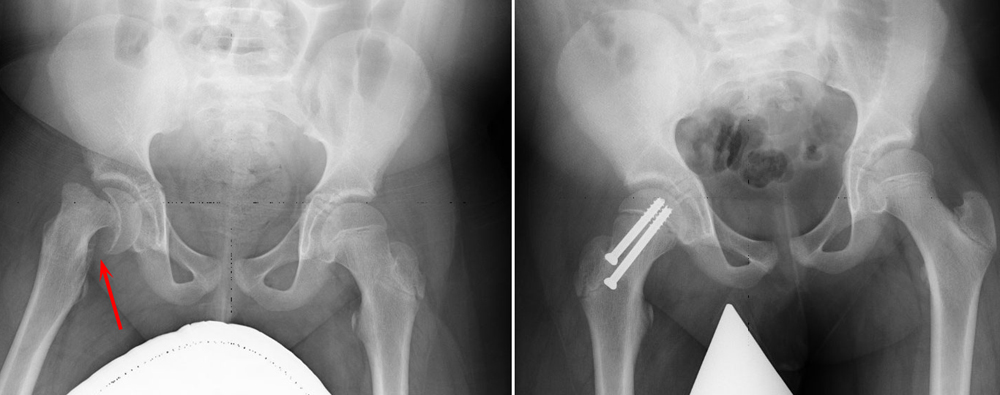

Open reduction. In patients with unstable SCFE, the doctor may first make an open incision in the hip, then gently reduce (manipulate) the head of the femur back into its normal anatomic position.

The doctor will then insert one or two metal screws to hold the bone in place until the growth plate closes. This is a more extensive procedure and requires a longer recovery time.

Open reduction

(Left) Preoperative X-ray of an unstable SCFE . (Right) Postoperative X-ray shows that the femoral head has been manipulated back into place and screws have been inserted to hold it in place.

Reproduced from Weber MD, Naujoks R, Smith B: Slipped capital femoral epiphysis. Orthopaedic Knowledge Online Journal 2008; 6(2). Accessed June 2016.